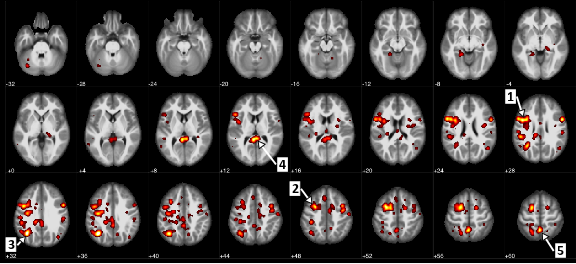

כאן, אנו רואים את אזורי המוח שהראו הבדל מובהק סטטיסטית בין חולים עם סכיזופרניה וחולים ללא זה. לדוגמה, חץ 1 מזהה את gyrus הפריסנטלי, או את הקורטקס המוטורי, ואת החץ 5 מסמן את precuneus, אשר כרוך עיבוד מידע חזותי.